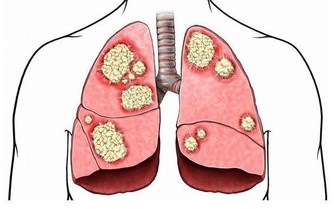

不讓「胃病變胃癌」!一定要這樣吃,晚知道後悔一輩子!趕快改過來!!

下班回家後到了七八點才好好的吃一頓晚飯,而與之類似的一系列壞習慣使胃癌患者越來越多。

直到今年2月過完年,他的發現自己的胃會經常疼痛,

去了醫院做了檢查才直到出現了胃部病變,需要手術,如果再晚些治療可能會發展成胃癌……